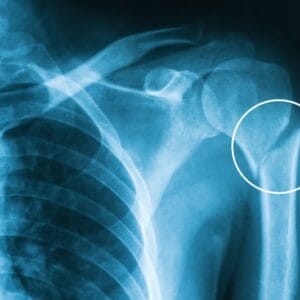

The Role of Genetics in Arm Injuries

Arm Patient informationArm injuries are a common concern for both athletes and non-athletes alike, ranging from mild muscle strains to severe tendon tears and fractures. While environmental factors like trauma, repetitive motions, and improper technique play significant roles, recent research highlights the influence of genetics on arm injury susceptibility. Understanding this genetic